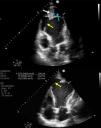

Imágenes en Medicina Intensiva

Shock cardiogénico por gran pseudoaneurisma apical del ventrículo izquierdo: una complicación infrecuente

Cardiogenic shock due to a large apical pseudoaneurysm of the left ventricle: A rare complication